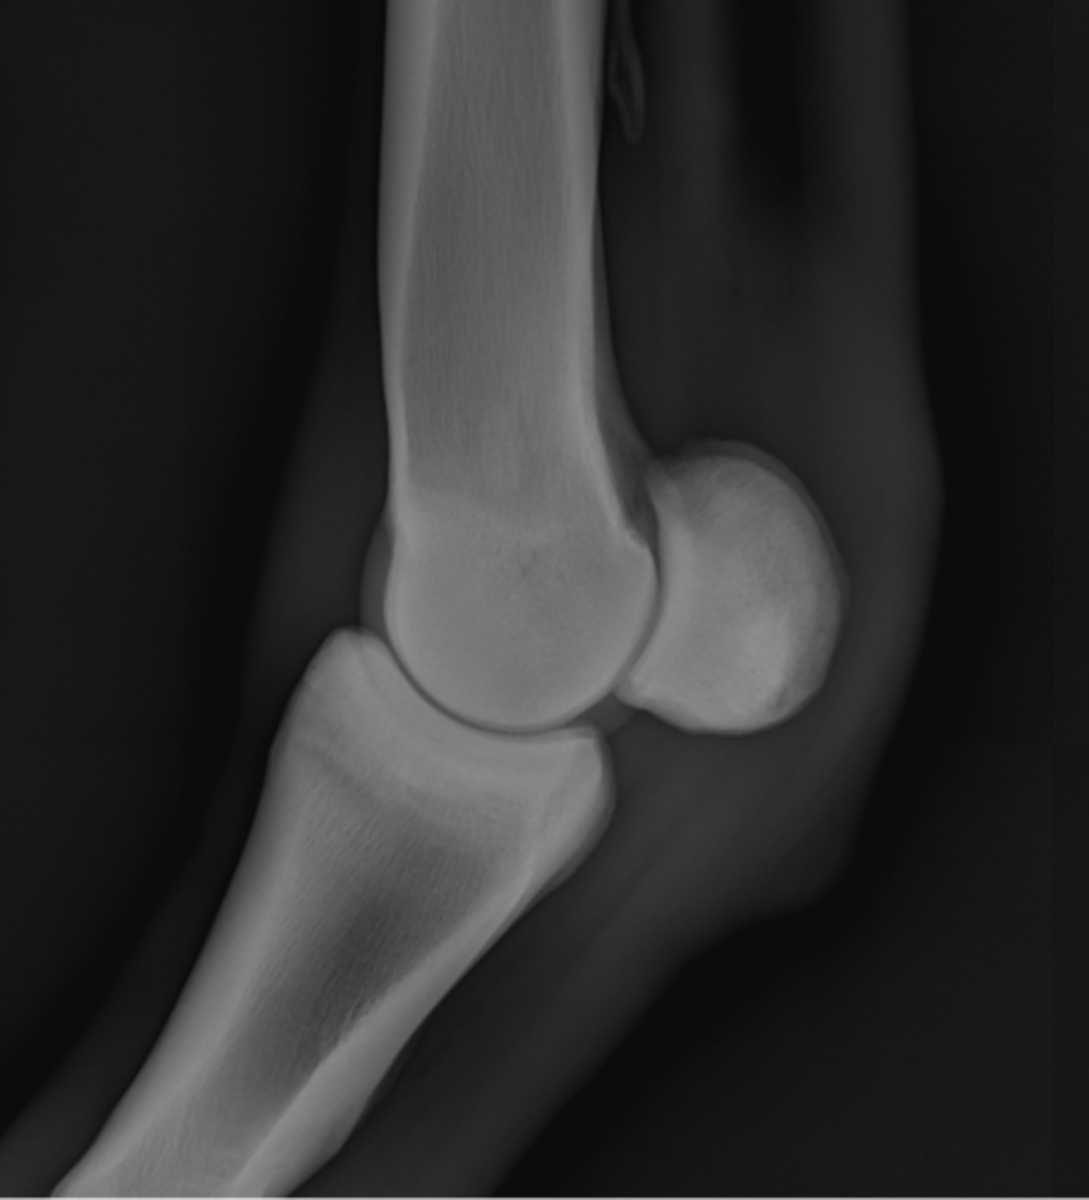

Fetlock joint, LM

ID joint and view